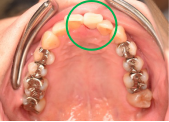

女性 Yさん 60代 (オールセラミック冠)

主訴

以前治療した右下の犬歯が、虫歯になり色が変わってきているので、治したい。

治療内容

根管治療をし、オールセラミック冠を被せました。

所感

神経が取り除かれ、歯自体が変色し、虫歯になっていました。根管治療をし、ファイバーコアを入れ、オールセラミック冠を被せました。

オールセラミック冠1本(失活歯):¥104,500(税込)

Before

After